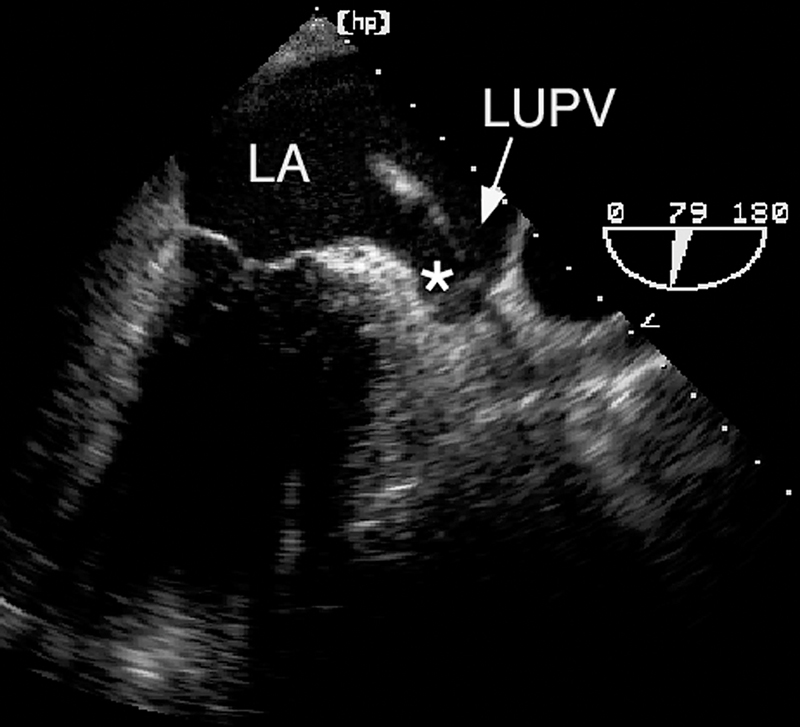

فحوصات تشخيصية لبعض امراض القلب والشرايين التاجية